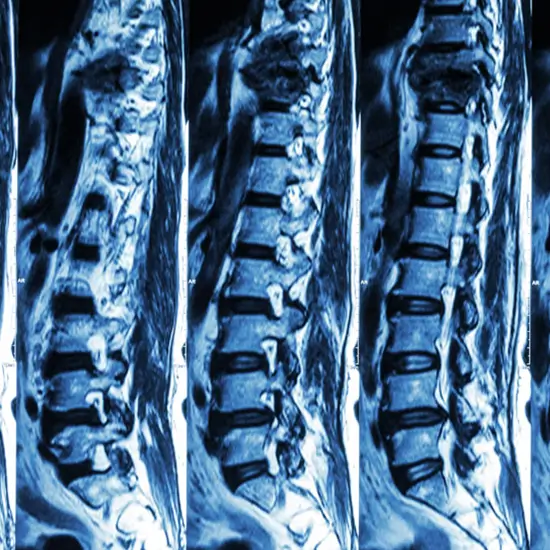

CT (Computed Tomography) of the spine with contrast media is a type of imaging scan used to diagnose and detect spinal column damage in injured patients. Contrast media is given to the patient for this scan in order to make the specific organ or tissue under study more visible. It is a quick procedure that provides more detailed information about the vertebrae, or spine bones, tissues, other spinal structures, injuries, and diseases.

A CT scan spine with contrast is recommended by doctors to evaluate the spine for a herniated disc, spinal tumours, the extent of spinal injuries, spinal structural anomalies such as spina bifida, blood vessel malformations, and a variety of other conditions. It is also used to assess the effects of spinal treatment.